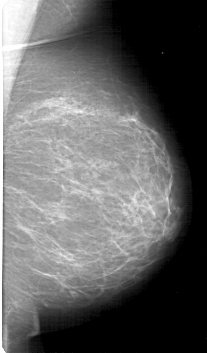

D_4126_1.LEFT_CC

LEFT_CC LINES 5296 PIXELS_PER_LINE 3166 BITS_PER_PIXEL 12 RESOLUTION 43.5 NON_OVERLAY